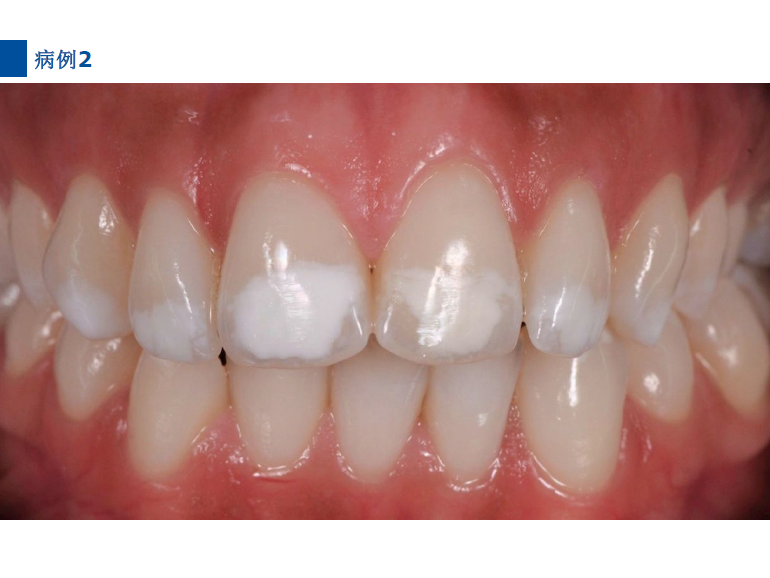

lcon渗透基于封闭釉质龋空隙的一种特殊树脂的渗透,封闭釉质龋小孔,从而阻断致龋酸传播途径,阻止龋病进一步发展。这种材料操作方法简单,对牙体组织损伤轻微,不用通过麻醉和磨切牙体来达到加固脱矿釉质,同时可以改变釉质龋表面的白色或棕色改变,达到美观修复效果,是对龋病微创治疗的突破。

二、爱康渗透树脂唇颊面装Icon Caries Infiltrant – vestibular,治疗唇颊面釉质早期龋。(整个套装包含一次治疗两至三个早期龋损所需的材料。一次性使用,如果邻牙有类似病变可一并治疗)。

7、旋转注射器柄部将足量材料涂布于已被酸蚀的龋损表面之上,等待3分钟,并用棉球去除多余材料。不要在牙椅照明灯直射下在前牙唇面涂布树脂。)

9、将一新的注射头装在含爱康渗透树脂Icon-Infiltrant的注射器上,重复步骤7-8.等待1分钟,光照40秒。